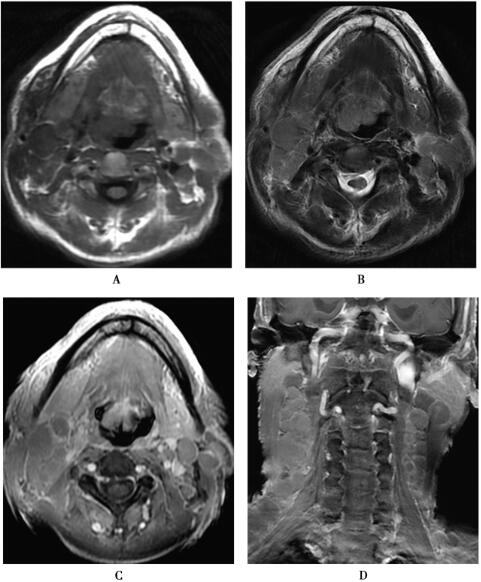

应用3.0T超导型MRI扫描仪(HDx,GE),8通道头颈联合线圈。SE联合水抑制脉冲序列获取体轴横断位T1WI(TR/TE=1996.76ms/28.2ms,TI=860ms),6mm层厚,2mm间隔,512×512矩阵,280mm视野,螺旋桨成像加脂肪抑制体轴横断位T2WI(TR/TE=7200ms/117.38ms),6mm层厚,2mm间隔,512×512矩阵,240mm视野,冠状位T2WI-IDEAL脉冲序列(TR/TE=3700ms/70.06ms),6mm层厚,1mm间隔,512×512矩阵,220mm视野。应用钆喷酸葡胺(剂量0.1mmol/kg体重)进行MRI增强扫描,流率2.5ml/s,获得SE联合FSPGR技术体轴横断位T1WI(图1)。

图1 口咽部恶性淋巴瘤

1.口咽部恶性淋巴瘤:口咽部可见不规则软组织肿块,T1WI呈等低信号,T2WI呈高信号,增强扫描口咽部病灶及淋巴结轻度强化,未见坏死。

口咽部淋巴组织十分丰富,腭扁桃体、舌扁桃体、软腭、咽侧壁及鼻咽部的咽鼓管扁桃体均含丰富的淋巴组织,它们构筑成环形淋巴管网组织,称为咽淋巴环,即韦氏环(Waldeyer ring),这些淋巴结与颈部淋巴结群相连通,淋巴瘤易沿黏膜淋巴管向周围蔓延,病变累及范围广泛。绝大多数口咽部淋巴瘤为非霍奇金淋巴瘤(NHL),少数为霍奇金淋巴瘤(HD),多为B细胞来源,以青壮年多见。本病例具有口咽恶性淋巴瘤的影像学特征性表现,MRI示颈双侧多发淋巴结肿大,融合成较大团块,T1WI为等信号或略低信号,T2WI为高信号,增强扫描病灶轻度强化。通常咽旁间隙及相邻结构不受累,淋巴瘤很发生深部侵犯,肿块较大时咽旁间隙仅受推移变窄。而口咽癌多为单侧发病,边界不清,外侵明显,病灶内部常见坏死,囊变,邻近骨骼常受侵犯,口咽癌血供丰富,增强扫描多有强化及大片坏死。